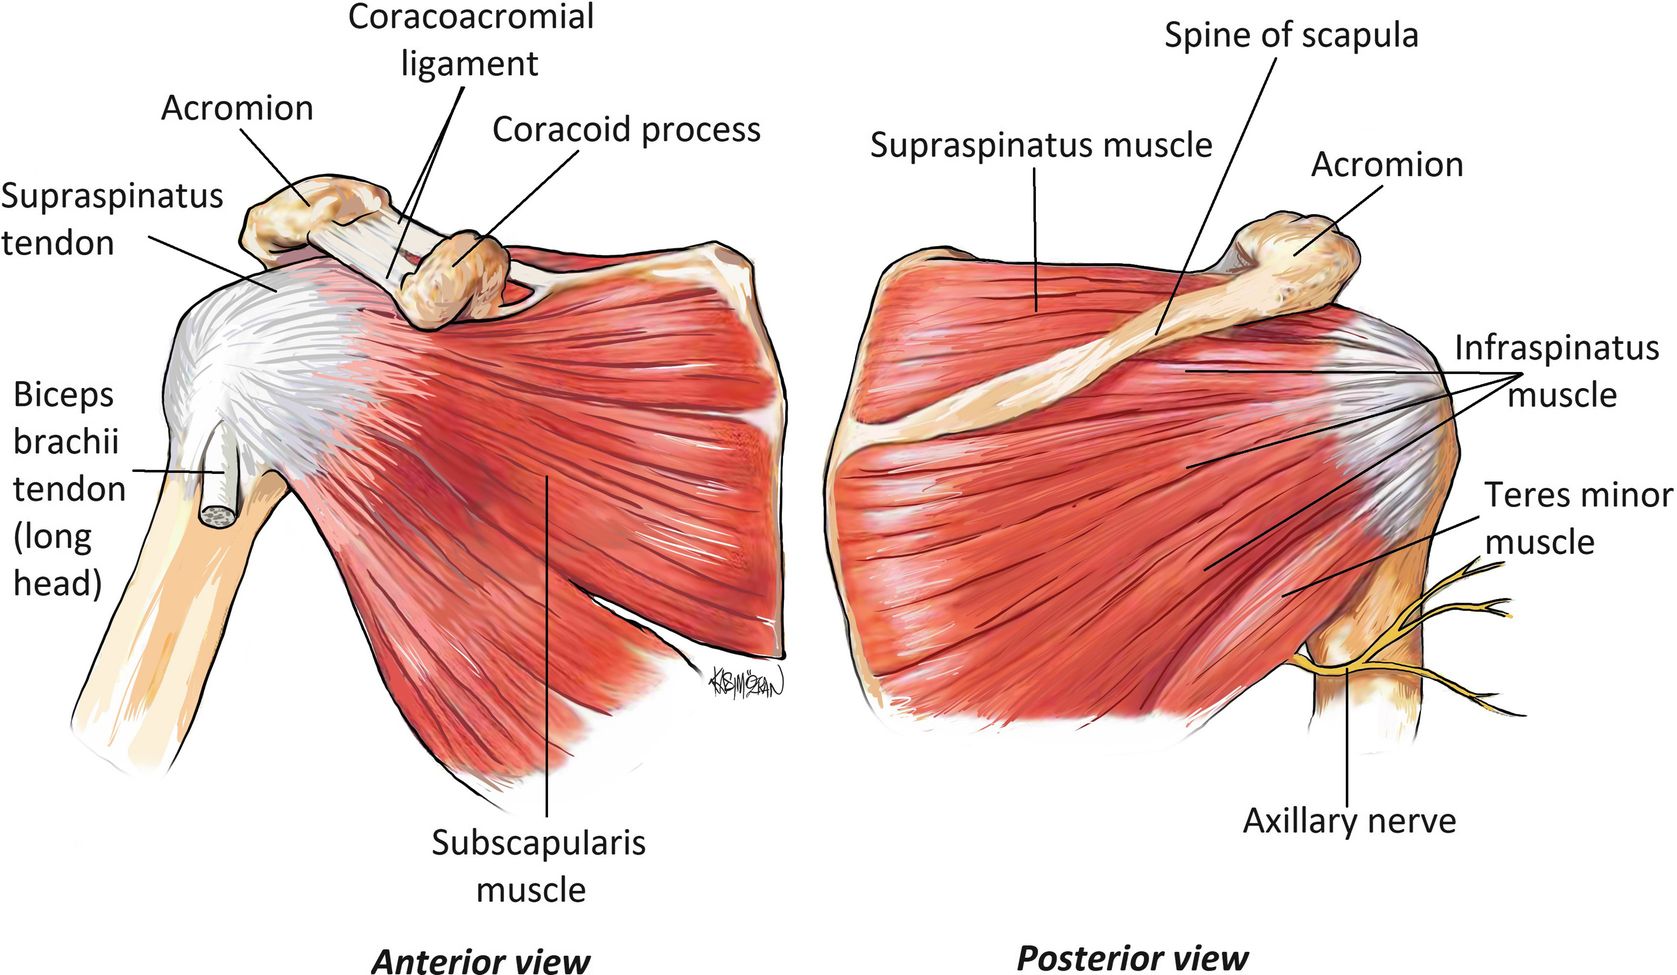

Фотографии мышц ротаторной манжеты плеча